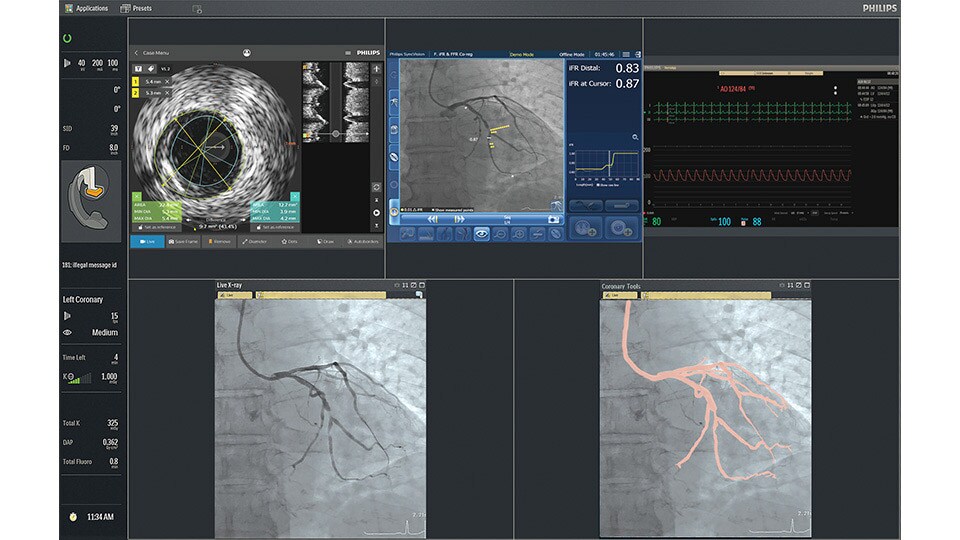

IntraSight

An interventional applications workspace that brings physiology, imaging and angiographic guidance tools together to optimize treatment plans.

iFR

Only Philips instant-wave free radio (iFR) has co-registration for advanced physiologic guidance, allowing you to precisely determine lesion location and severity.

iFR Co-registration

As an alternative or adjunct to IVUS Co-registration, iFR pullback can be co-registered onto the angiogram to assess both the degree and length of vessel stenosis.